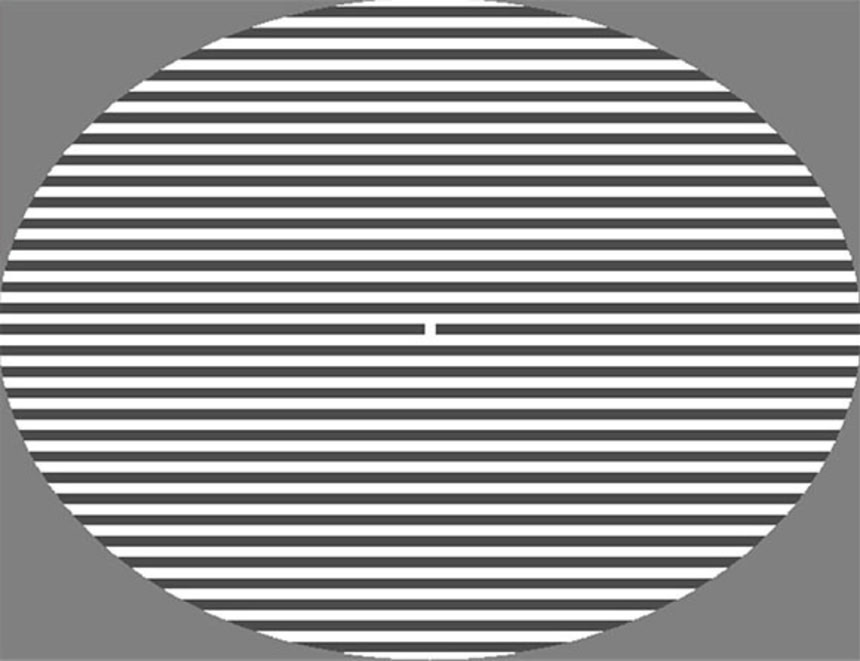

この研究では被験者60名(うち半分が片頭痛持ち)に縞模様の格子パターンを見つめてもらうという実験を行った。

格子パターンは全部で3種類あり、そのうちの1つがランダムに選ばれて12秒間表示される。被験者は縞模様の中央にある点を見つめながら、そのときに感じた不快感(目の痛みや疲れ、頭痛、めまいなど)や、何か変わったもの(影や幻覚など)が見えればそれを報告する。

この画像を大きなサイズで見る実験に使用された格子パターン

image credit:NeuroImage: Clinical 2019,Fong et al.